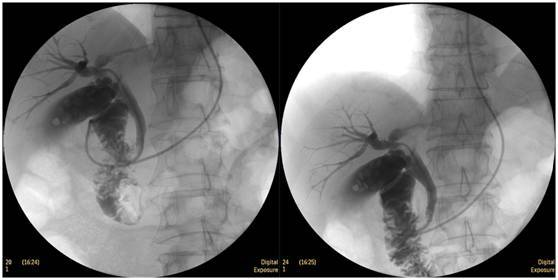

搭配DRCF的ERCP診斷優勢:

膽囊結石

ERCP膽囊顯影,見多枚結石影。

鼻膽管造影

立位注入造影劑,膽總管顯影好,稍擴張,未見結石影。

膽總管結石

柱狀球囊擴張完全,膽總管擴張,下段見充盈缺損影。

膽總管擴張,下段見明顯充盈缺損(上圖為反片且局部放大后效果)

柱狀球囊擴張膽總管下段及乳頭(上圖為使用取石網籃取石)。

食管惡性腫瘤

食管癌并狹窄內鏡下擴張支架植入術,支架在脊柱背景下依然能清晰顯示。